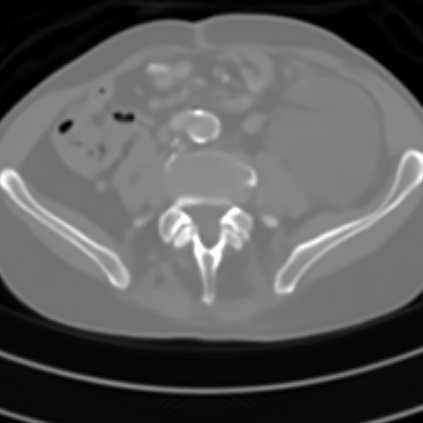

Sparse-view computed tomography (CT) -- using a small number of projections for tomographic reconstruction -- enables much lower radiation dose to patients and accelerated data acquisition. The reconstructed images, however, suffer from strong artifacts, greatly limiting their diagnostic value. Current trends for sparse-view CT turn to the raw data for better information recovery. The resultant dual-domain methods, nonetheless, suffer from secondary artifacts, especially in ultra-sparse view scenarios, and their generalization to other scanners/protocols is greatly limited. A crucial question arises: have the image post-processing methods reached the limit? Our answer is not yet. In this paper, we stick to image post-processing methods due to great flexibility and propose global representation (GloRe) distillation framework for sparse-view CT, termed GloReDi. First, we propose to learn GloRe with Fourier convolution, so each element in GloRe has an image-wide receptive field. Second, unlike methods that only use the full-view images for supervision, we propose to distill GloRe from intermediate-view reconstructed images that are readily available but not explored in previous literature. The success of GloRe distillation is attributed to two key components: representation directional distillation to align the GloRe directions, and band-pass-specific contrastive distillation to gain clinically important details. Extensive experiments demonstrate the superiority of the proposed GloReDi over the state-of-the-art methods, including dual-domain ones. The source code is available at https://github.com/longzilicart/GloReDi.